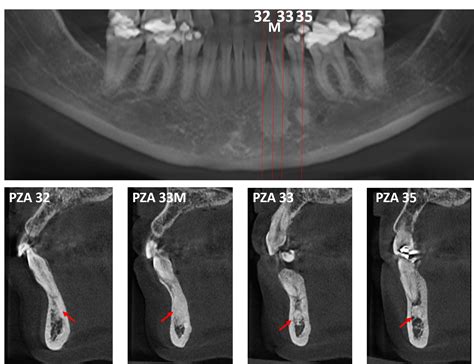

El diagnóstico de la osteoesclerosis idiopática dental se basa principalmente en hallazgos radiográficos. La lesión puede verse en las radiografías y en los TAC. El hueso es más denso y aparece más opaco (más blanco en la radiografía). Es una lesión asintomática.

En la evaluación radiográfica, las osteoesclerosis idiopáticas pueden detectarse en varios tamaños, que van de 2 o 3 mm a 1 o 2 cm de diámetro, o las lesiones pueden ser muy grandes, abarcando casi toda la altura del cuerpo de la mandíbula.

- Tomografía Computarizada de Haz Cónico (CBCT): Permite una evaluación tridimensional precisa de la lesión.